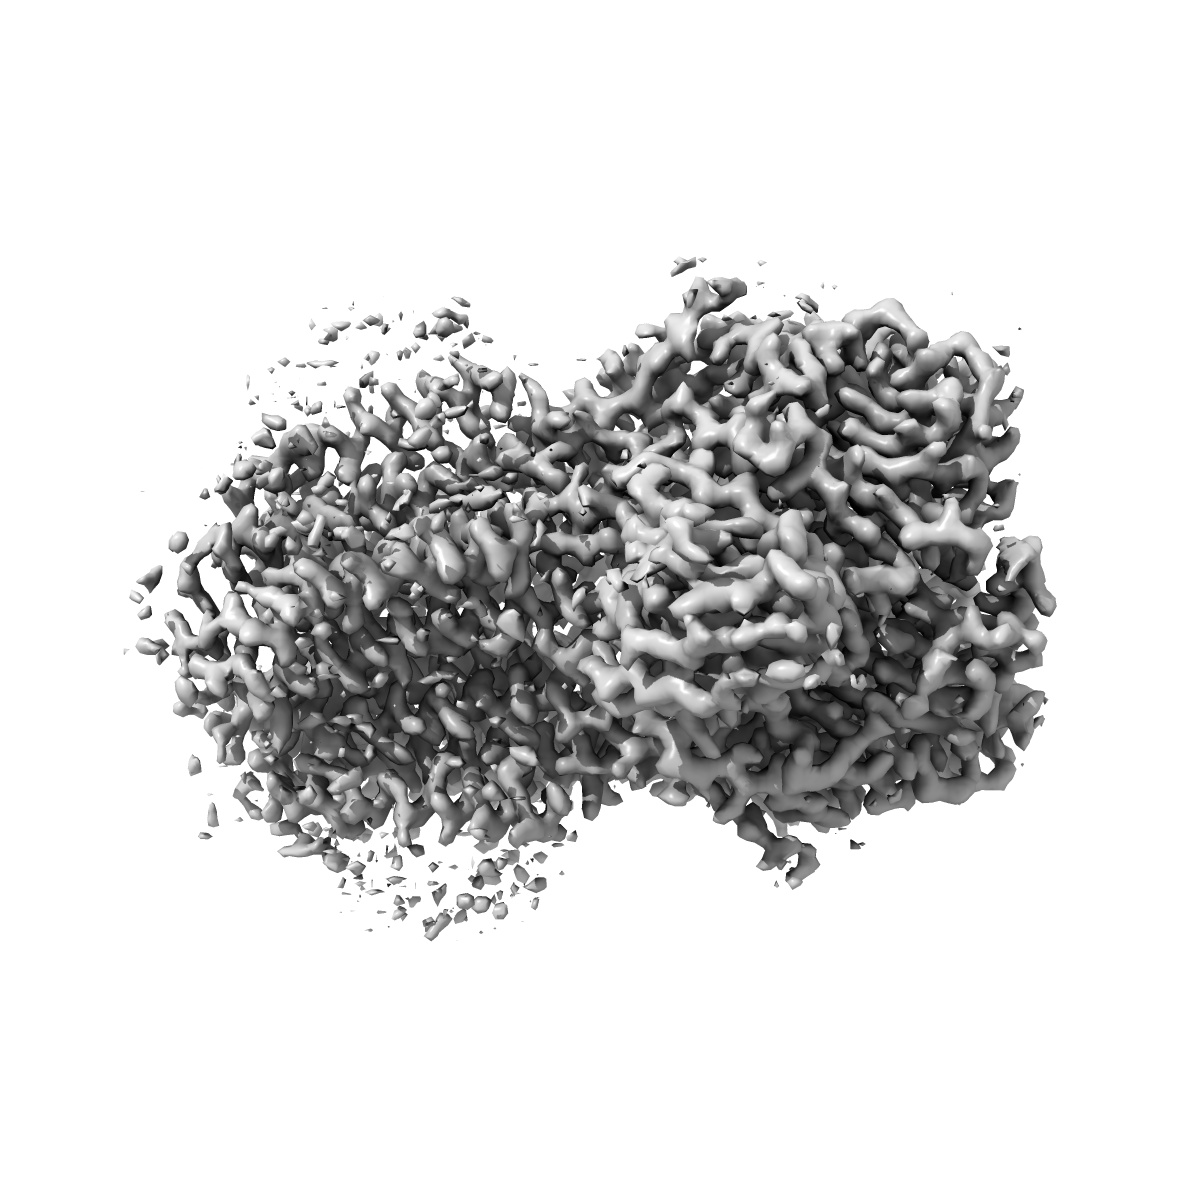

Cryo-EM structure of the human synaptic alpha1-beta3-gamma2 GABAA receptor in complex with Megabody38 in a lipid nanodisc

Sample: Human alpha1-beta3-gamma2 GABA-A receptor in complex with Megabody38 and in lipid nanodiscs

Fitted models: 6i53

Cryo-EM structure of the human alpha 1 beta 3 gamma 2 GABAAreceptor in a lipid bilayer.